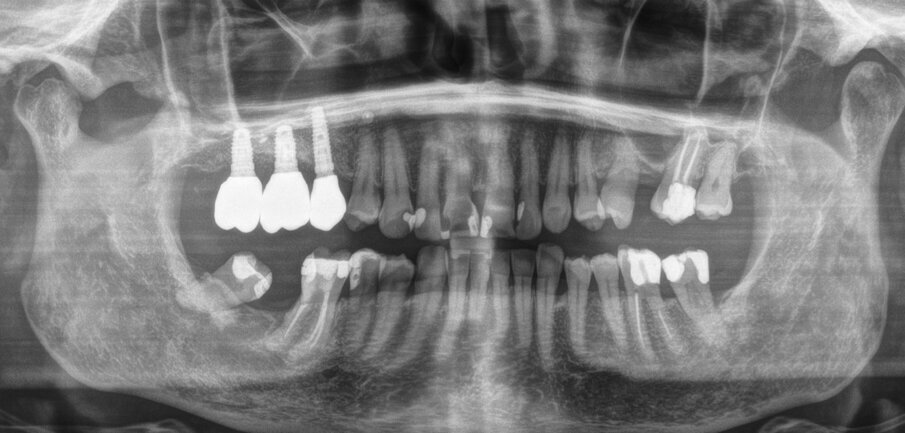

Una paziente di 62 anni, ASA I, non fumatrice e non diabetica, con malattia parodontale precedentemente trattata, si è presentata per una riabilitazione implanto-protesica del mascellare superiore (Fig. 1). L’analisi radiografica, eseguita tramite ortopantomografia (OPT) e tomografia computerizzata cone-beam (CBCT), ha rilevato la presenza di un difetto osseo verticale nel primo sestante, dovuto alla completa perdita del processo alveolare (Figg. 2, 3). Dopo aver discusso con la paziente le possibilità di trattamento, è stato accettato il trattamento proposto come prima scelta, ovvero la ricostruzione ossea del processo alveolare e la successiva riabilitazione mediante corone singole su impianti.